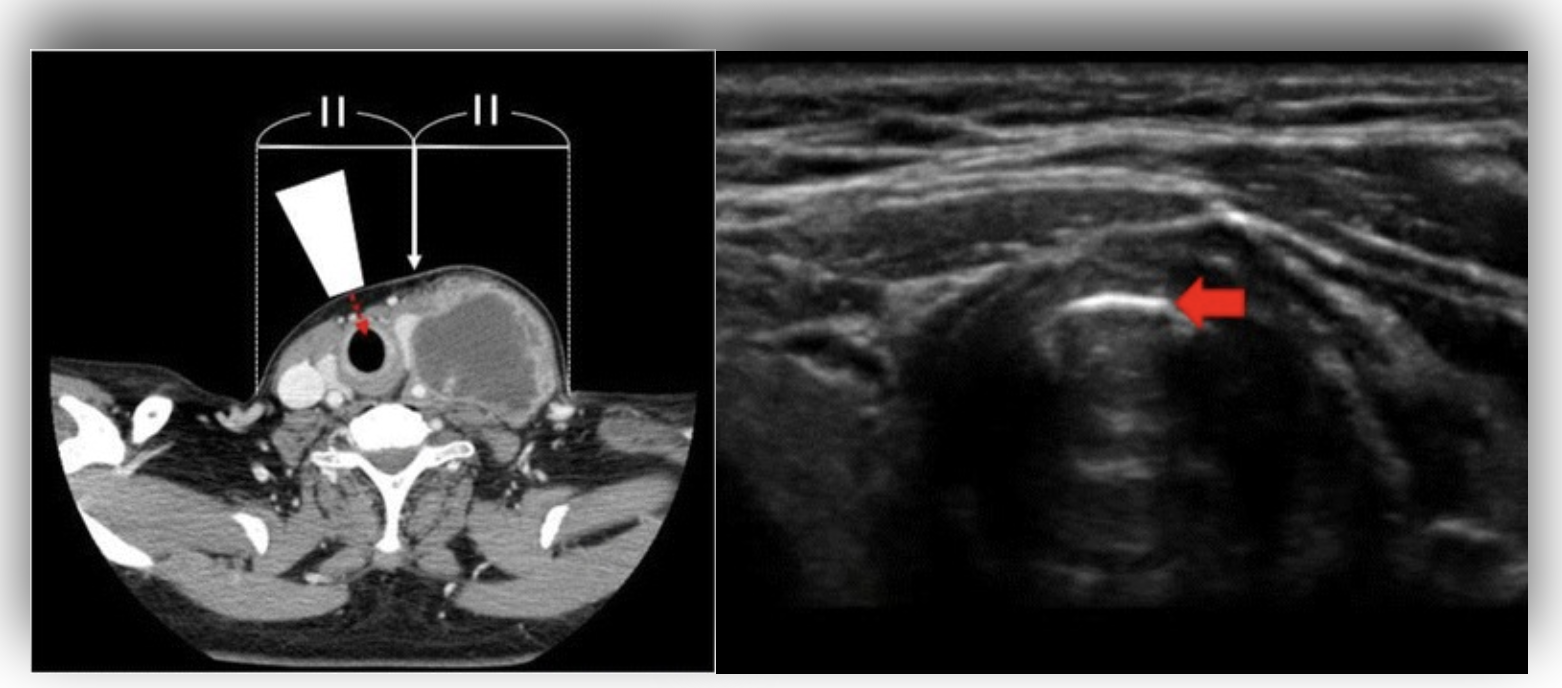

Image 2. A transverse POCUS image of the cricothyroid membrane (RIGHT) is displayed. The hyperechoic membrane with air filled larynx is seen in the far field. Air posterior to a reflective surface creates reverberation artifact or A-lines. This is seen deep to the membrane. The image to the LEFT is a CT showing the laterally displaced cricothyroid membrane.

Multiple case series have described identifying the cricothyroid membrane under ultrasound guidance. A 2018 report describes a patient with a deep neck abscess that was admitted to the hospital for surgical drainage. Unfortunately, the patient developed progressive airway compromise prior to surgery and needed emergent airway control. Due to the swelling secondary to the abscess, the cricothyroid membrane could not be palpated and with the use of ultrasound was actually found to be much more lateral then what was initially predicted (2).